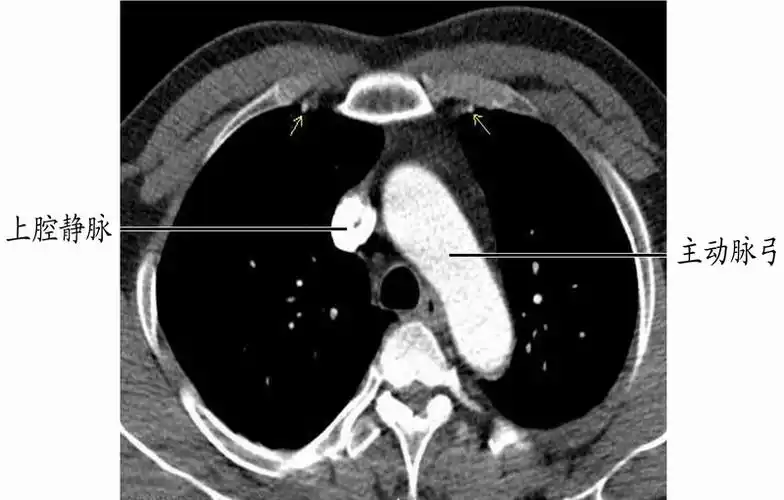

正常心脏大血管ebct增强扫描影像学表现-医学影像图